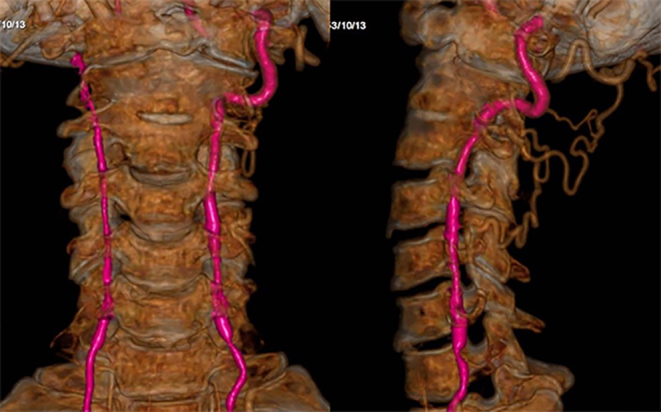

Radiography is of importance in the diagnosis of atlantoaxial dislocation (AAD), and it is the basic imaging technique. However, it should not be the sole diagnostic modality, especially in complex or unclear cases. Conventional X-ray includes an open-mouth odontoid view and a cross-table lateral view, and careful study of radiological findings is crucial to give an early diagnosis of AAD. Lateral flexion-extension dynamic views are only used as an additional supplement in some special cases. Although X-ray images are enough to diagnose AAD in most cases, some patients suspected with AAD should be evaluated with the readily available and quick CT scan. If patients with AAD have symptoms of spinal cord and medullary compression, apart from conventional radiographs, a combination of high-quality CT and MRI of cervical spine are necessary for the diagnosis and choice of treatment. For patients with AAD, both the thin slice CT scanning with coronal, sagittal and three-dimensional reconstruction images and MRI of cervical spine are fundamental to surgical planning. Clinical classifications of AAD associated with imaging are useful in determining treatment strategies. The present study reviews publications on imaging and clinical classification of AAD to aid the clinician in the evaluation and management of these dislocations.